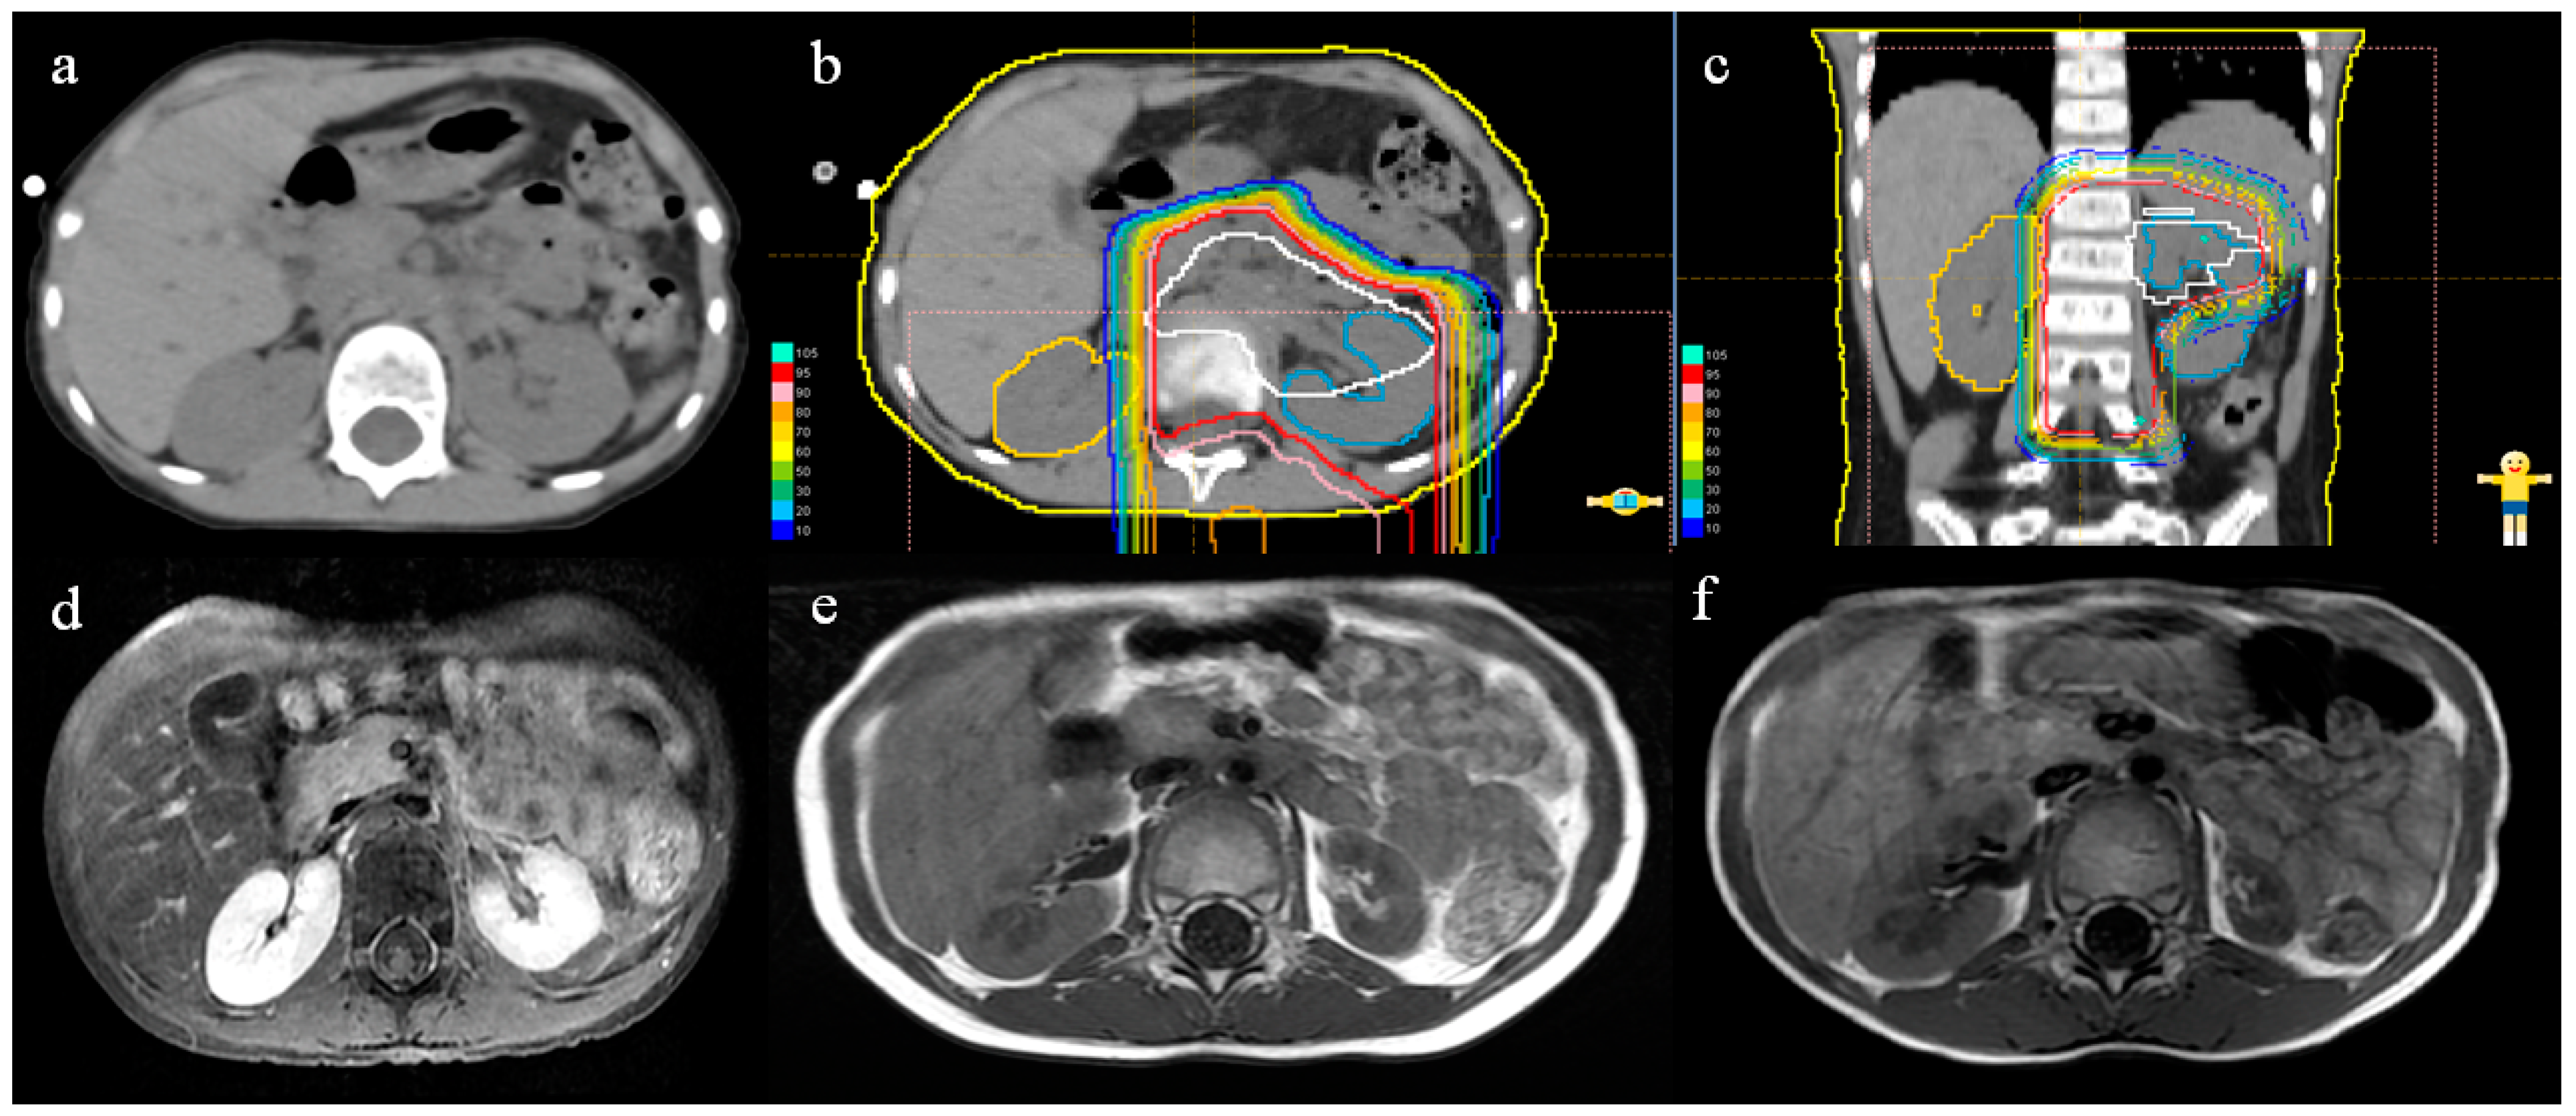

2.2. Proton Beam Therapy